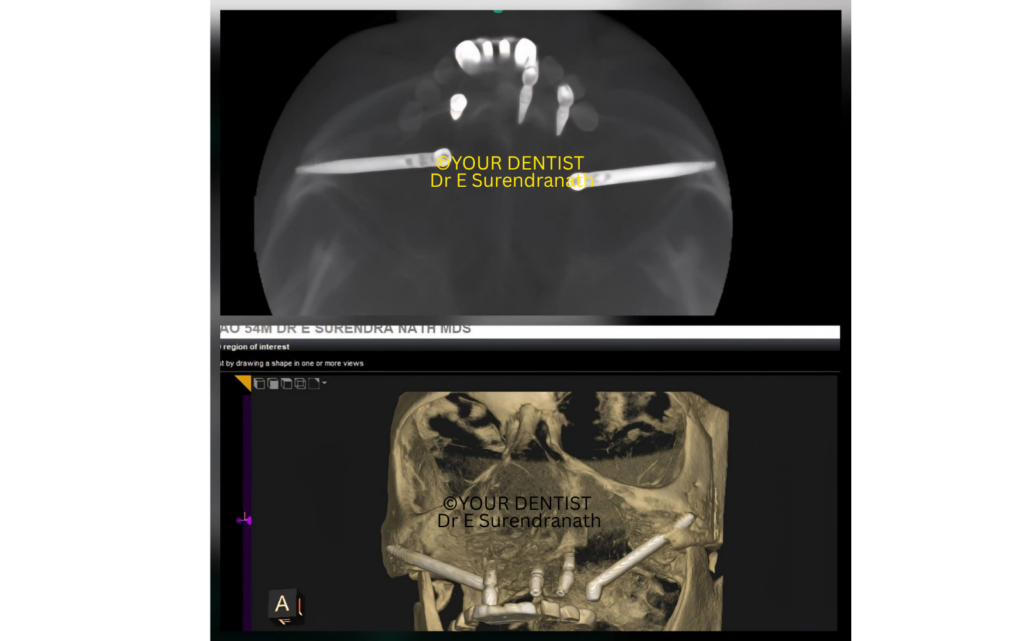

The patient presented with a severely resorbed upper jaw and failing dentition. The posterior maxilla showed very limited residual bone measuring just 2mm, and mind you, the minimum implant size is 10 mm long, making conventional implant placement in the back region highly unfavourable. In such cases, the major difficulty is not simply replacing teeth, but creating a stable foundation strong enough to support a fixed prosthesis immediately and predictably.

On radiographic evaluation, the upper jaw showed advanced bone loss with very poor support in the posterior segments. It also showed us that the sinus is highly pneumatized, that is, the sinus expanded much at the cost of the jawbone, and even the anterior jawbone is not in a position to accommodate 4 implants. This is exactly the kind of situation where zygomatic implants become a valuable treatment option.

Fig 1.

Full arch implant molar positioning X-ray

In Fig 1, you can see all three X-rays together: the Pre Op, the Mid Op, and the Post Op.

You can observe in the mid op that bone is very Less in the front region of the upper jaw, and zero bone in the back region of the upper jaw.

The radiographs and 3D views show the zygomatic implants extending into the zygomatic buttress region bilaterally, with the prosthetic platform emerging in a highly favorable distal position. This is an important biomechanical advantage because it helps us support a fixed full-arch prosthesis more efficiently. This can be clearly seen in the CBCT images that are in Fig 4.

Fig 4